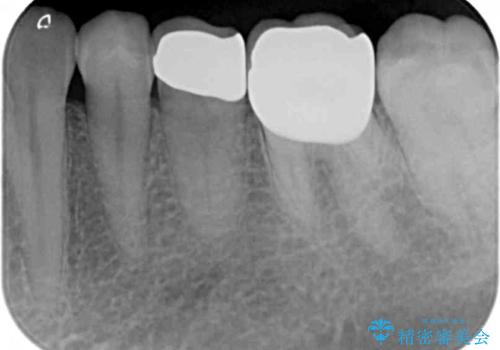

X線検査を行なったところ、以前他院にて治療した白い詰め物の下に虫歯の再発を認めました。

詰め物を除去したのち、虫歯を丁寧に除去することで神経を保存しながらセラミッククラウンによる補綴治療を行うことができました。

外から見て白くきれいな修復が為されていたとしても、内部で虫歯が再発していることは多々あります。

違和感を感じたら早期にX線検査を行い、神経が保存できるうちに治療を行うことが重要です。